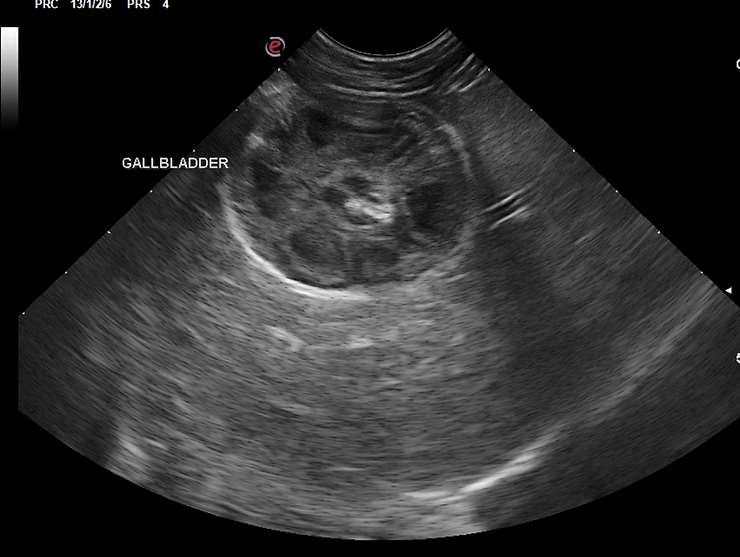

•Abdominalultrasound(“swisscheeseliver”)